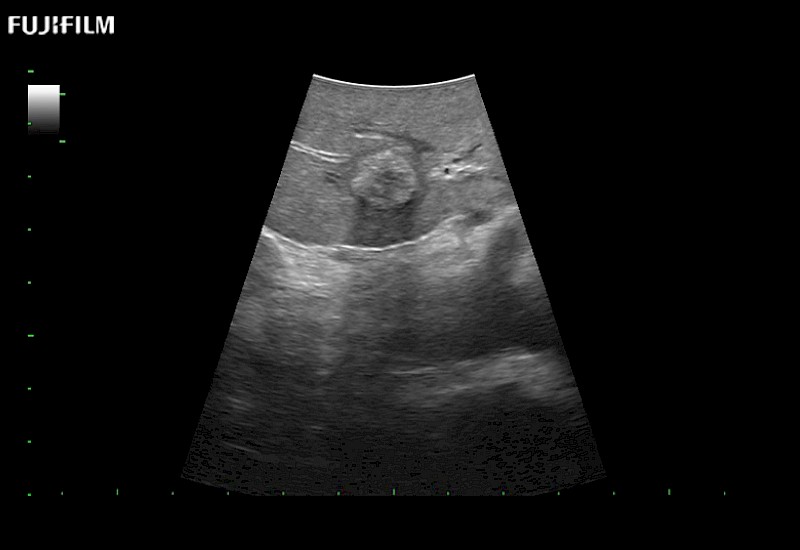

Exclusive linear array 4-way laparoscopic transducer for better visualization of targeted lesions.

Main Specifications: